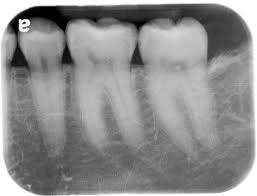

• 2.       Bite-wings x-rays

• Image result for xrays in dentistry